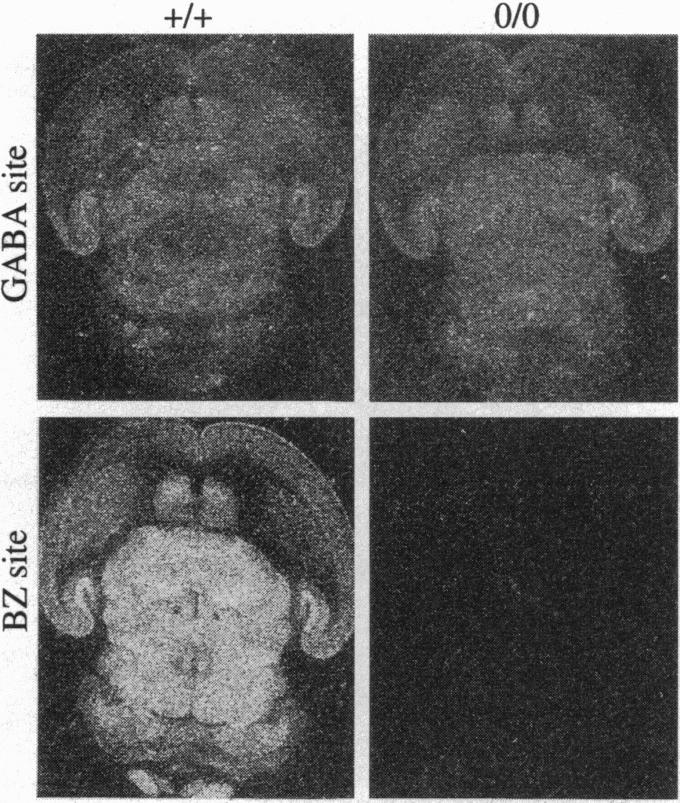

Vigilance, anxiety, epileptic activity, and muscle tone can be modulated by drugs acting at the benzodiazepine (BZ) site of gamma-aminobutyric acid type A (GABAA) receptors. In vivo, BZ sites are potential targets for endogenous ligands regulating the corresponding central nervous system states. To assess the physiological relevance of BZ sites, mice were generated containing GABAA receptors devoid of BZ sites. Following targeted disruption of the gamma 2 subunit gene, 94% of the BZ sites were absent in brain of neonatal mice, while the number of GABA sites was only slightly reduced. Except for the gamma 2 subunit, the level of expression and the regional and cellular distribution of the major GABAA receptor subunits were unaltered. The single channel main conductance level and the Hill coefficient were reduced to values consistent with recombinant GABAA receptors composed of alpha and beta subunits. The GABA response was potentiated by pentobarbital but not by flunitrazepam. Diazepam was inactive behaviorally. Thus, the gamma 2 subunit is dispensable for the assembly of functional GABAA receptors but is required for normal channel conductance and the formation of BZ sites in vivo. BZ sites are not essential for embryonic development, as suggested by the normal body weight and histology of newborn mice. Postnatally, however, the reduced GABAA receptor function is associated with retarded growth, sensorimotor dysfunction, and drastically reduced life-span. The lack of postnatal GABAA receptor regulation by endogenous ligands of BZ sites might contribute to this phenotype.

作用于γ-氨基丁酸A型(GABAA)受体苯二氮䓬(BZ)位点的药物可调节警觉性、焦虑、癫痫活动和肌张力。在体内,BZ位点是调节相应中枢神经系统状态的内源性配体的潜在靶点。为了评估BZ位点的生理相关性,构建了缺乏BZ位点的GABAA受体的小鼠。在有针对性地破坏γ2亚基基因后,新生小鼠大脑中94%的BZ位点缺失,而GABA位点的数量仅略有减少。除γ2亚基外,主要GABAA受体亚基的表达水平、区域和细胞分布均未改变。单通道主电导水平和希尔系数降低至与由α和β亚基组成的重组GABAA受体一致的值。戊巴比妥可增强GABA反应,但氟硝西泮则不能。地西泮在行为上无活性。因此,γ2亚基对于功能性GABAA受体的组装并非必需,但对于体内正常的通道电导和BZ位点的形成是必需的。如新生小鼠正常的体重和组织学所示,BZ位点对于胚胎发育并非必不可少。然而,在出生后,GABAA受体功能降低与生长迟缓、感觉运动功能障碍和寿命大幅缩短有关。出生后缺乏BZ位点的内源性配体对GABAA受体的调节可能导致这种表型。